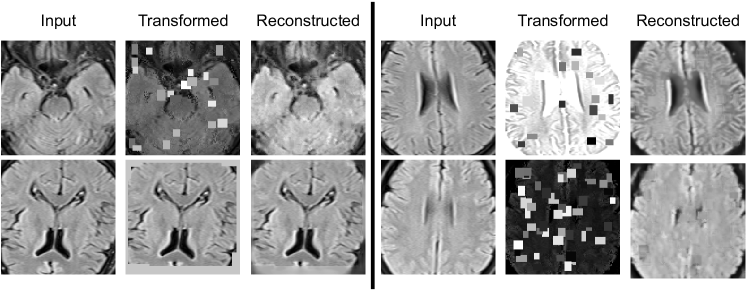

In this work, we use a self-supervised learning method to extract specific features of our data from multiple perspectives (appearance, texture, context, etc.) by combining three different supervision tasks that were proposed in “Models Genesis” [31]. Our model consists of a U-Net [25] with a ResNet [9] encoder. Each supervision task consists of a particular transformation and reconstructing the original image from the transformed one (see Fig. 3). Finally, the encoder part of the network is fine-tuned for the target classification task.

In this document, we provide additional materials to supplement our main submission. In the first section, the dataset which is provided and used for this paper is investigated. In the second section, we provide the mathematical details of Otsu Thresholding[23], which is used in pre-processing step. Third section illustrates four examples of our self-supervised training.

5.3 Self-Supervised Training Results Visualization